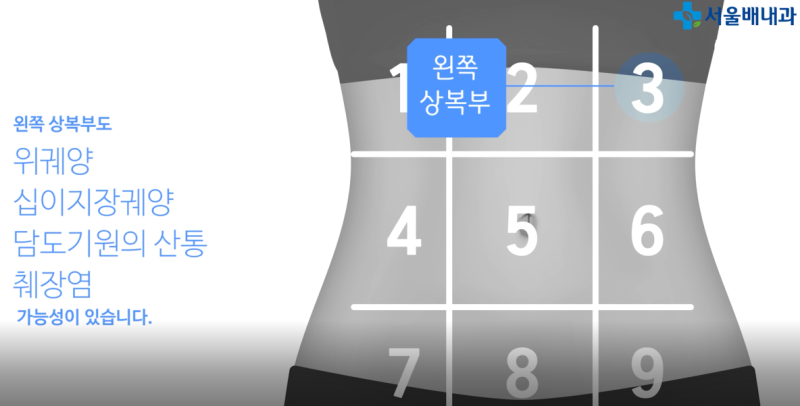

적어도 일주일에 한 번 정도는 염증 치료를 받으러 방문할 수 있지만, 그 과정에서 왼쪽 태반 밑에 남은 통증은 결국 관리가 필요해 비용과 시간 모두 비효율적으로 보였습니다.두통증은 왼쪽 태양과 관절염 등 심근통증으로 인한 근육 통증, 통증, 통증, 통증, 통증, 통증, 통증 등 근육 통증을 유발한다.그래서 저는 결심했습니다.나는 그것을 시도해봤어요.위 아래 통증에 직접 사용한 사용 후기사실, 초기 비용은 조금 높았지만, 제가 계속 사용하고 있다고 가정하는 것보다 훨씬 효율적이었습니다.제가 그것을 받았고, 우리가 예상했던 것보다 더 빨리 고통받는 지역보다 빨리 보살핌을 받았습니다.배가 위쪽에 있는 배가 아파요. 배가 위쪽에 통증을 호소했지만, 위쪽에 있는 근육에 통증이 심해졌다.나는 솔직히 즉각 반응을 보였다.사실 초기 비용은 조금 비쌌지만, 계속 사용한다고 가정하면 직접 가지러 가는 것보다 효율적이었습니다.제가 받아서 사용했는데, 생각보다 아픈 부위를 빨리 치료해 주었습니다.위의 오른쪽 구덩이의 통증 > 왼쪽 구덩이의 통증 > 위의 구덩이 아래의 통증 순서대로 아팠지만, 위의 구덩이 주위를 모두 사용한 후에는 안쪽에서 근육이 당기는 느낌이 사라졌습니다.저는 솔직히 즉각적인 반응에 놀랐습니다.이 방법은 오래전부터 전류를 통한 통증 관리의 일환으로 여러 기관에서 널리 사용되고 있어 집에서도 안심하고 사용하실 수 있습니다!한국에서 개발된 리무버인 줄 알았는데 아니었어요.유럽인들이 갑자기 고통을 준비하기 때문에 디럭스 스토리를 준비하기 어렵다.오른쪽 피치 통증을 위해 사용하면서 근육은 근육이 약간 느슨하게 느껴졌고, 근육이 약간 느슨하게 느껴졌다.전기가 있으면 안 아파요. 하지만 오른쪽 시원한 느낌은 기분이 좋을 것 같아요.높은 휴대성과 편리함으로 사용하기 좋습니다또 다른 장점은 일상 생활에서 운반할 수 있다는 것입니다.갑자기, 통증이 심해지고 숨을 쉴 때, 특히 숨을 들이고 숨을 쉴 때렸다.그리고 무의식적으로 이 자세를 취해서 고통을 느꼈을 때 내 일에 집중하기 힘들었다.하지만, 통증이 갑자기 올라가면, 내 옷을 벗기고, 옷 위에 올려서 호흡이 더 빨리 통증이 심해지고, 진통제가 더 빨리 치료하기가 더 빨라졌다.일상생활에서 휴대할 수 있고 원할 때 언제든지 사용할 수 있다는 점도 장점으로 꼽혔습니다.특히 몸을 뒤로 젖히거나 숨을 크게 쉴 때 갑자기 따끔거리고 통증이 느껴졌습니다.그리고 무의식적으로 이런 자세를 취하며 고통을 느낄 때, 잠시 지속되었기 때문에 일에 집중하기가 어려웠습니다.하지만 지금은 갑자기 통증이 높아지면 기기를 꺼내 옷에 붙이고 클릭하면 숨막히는 통증이 금방 진정되기 때문에 진통제를 먹는 것보다 훨씬 빨리 치료하는 것이 좋았습니다.오른쪽 태음순의 통증과 태음순 아래의 통증 외에도, 여러분은 피부와 근육이 위치한 곳이라면 어디서든 사용할 수 있습니다!저는 기계의 지원을 받아 그것을 썼습니다.